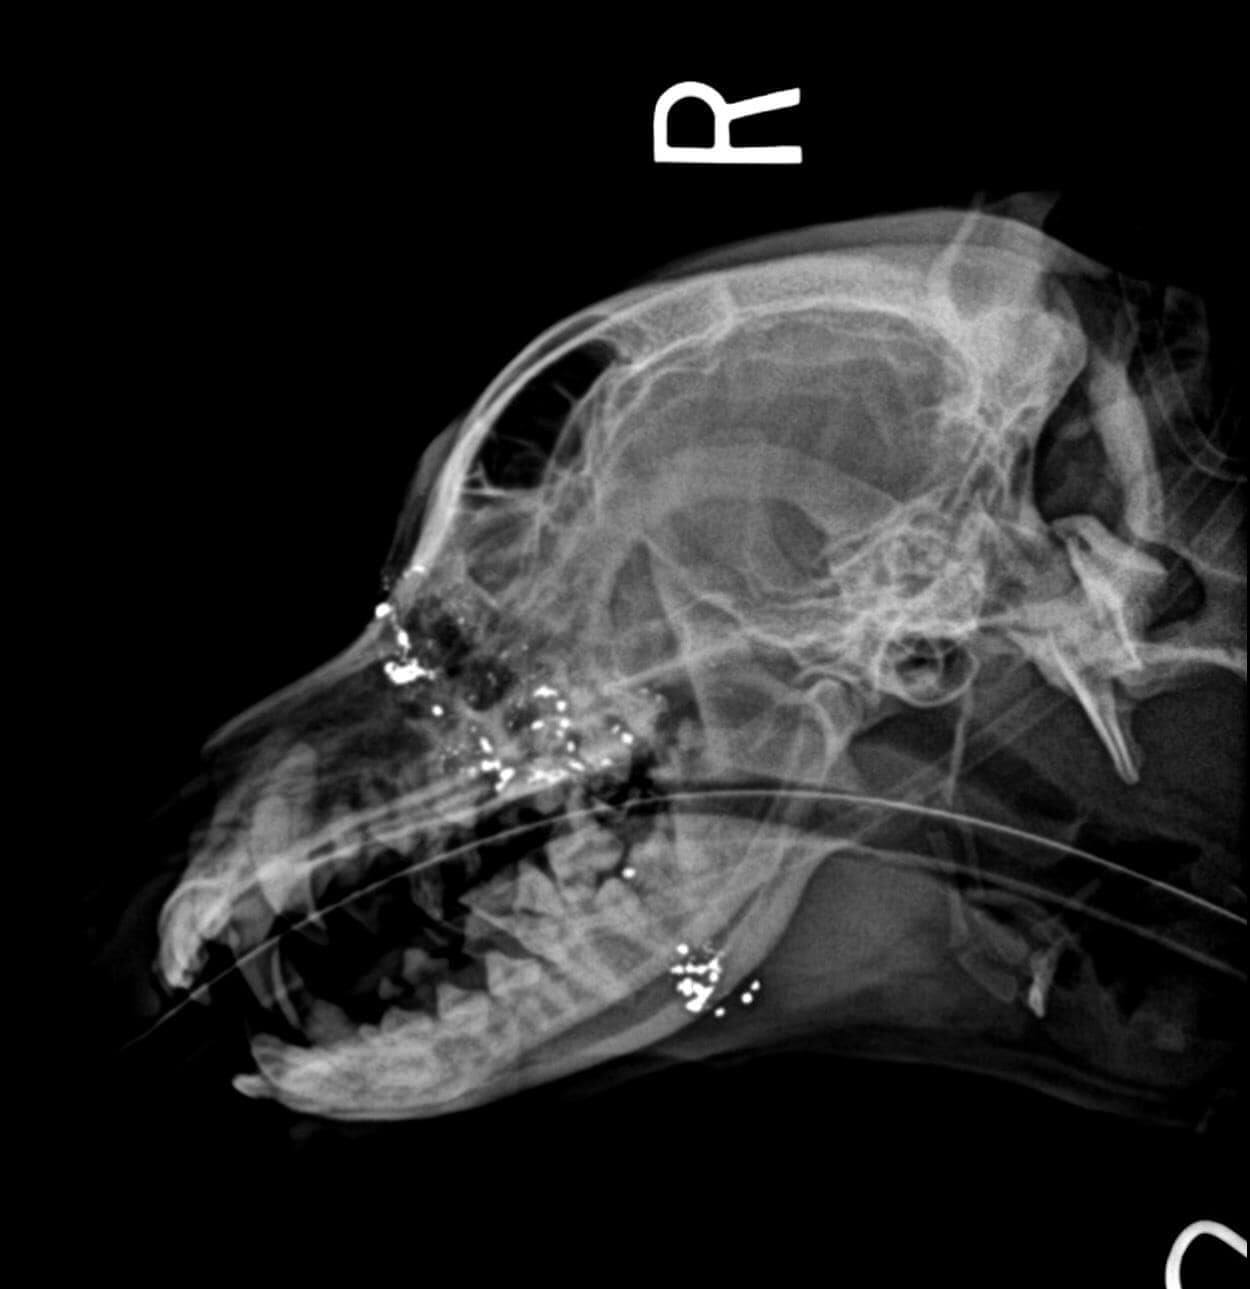

Dr. Alicia Royer cleaned away the dirt, and through the infection that had developed she spotted what looked very much like a gunshot wound. X-rays confirmed her suspicions. The dog had been shot at an angle that was slightly too steep and missed his brain. The bullet resulted in a large hole in the dog’s head causing damage to his airway and mouth. Couple his injuries with fleas, anemia and ear infections, Arthur would have to struggle to overcome his physical challenges to survive.

We are hopeful that Arthur will make a full recovery, but there are bullet fragments remaining. He may need specialty care to remove them. Only time will tell.